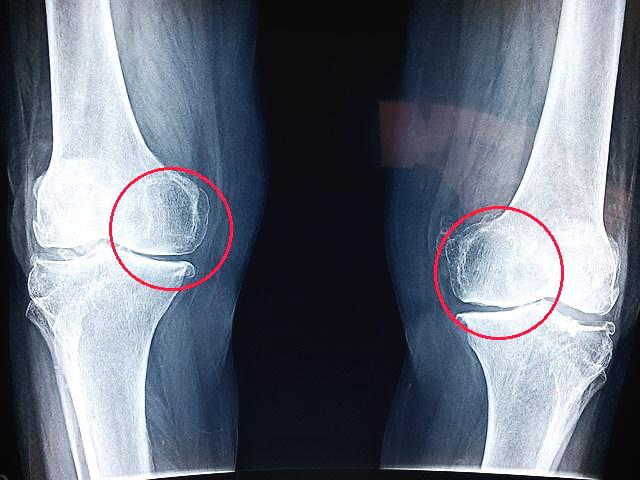

사람의 무릎 엑스레이 사진인데요

안쪽 뼈 크기가 바깥쪽보다 더 크다는 것을 알 수 있죠?

이렇게 무릎은 안쪽 관절을 더 크게 해서 안쪽으로 회전하고 굽히기 쉽도록 만들어졌습니다